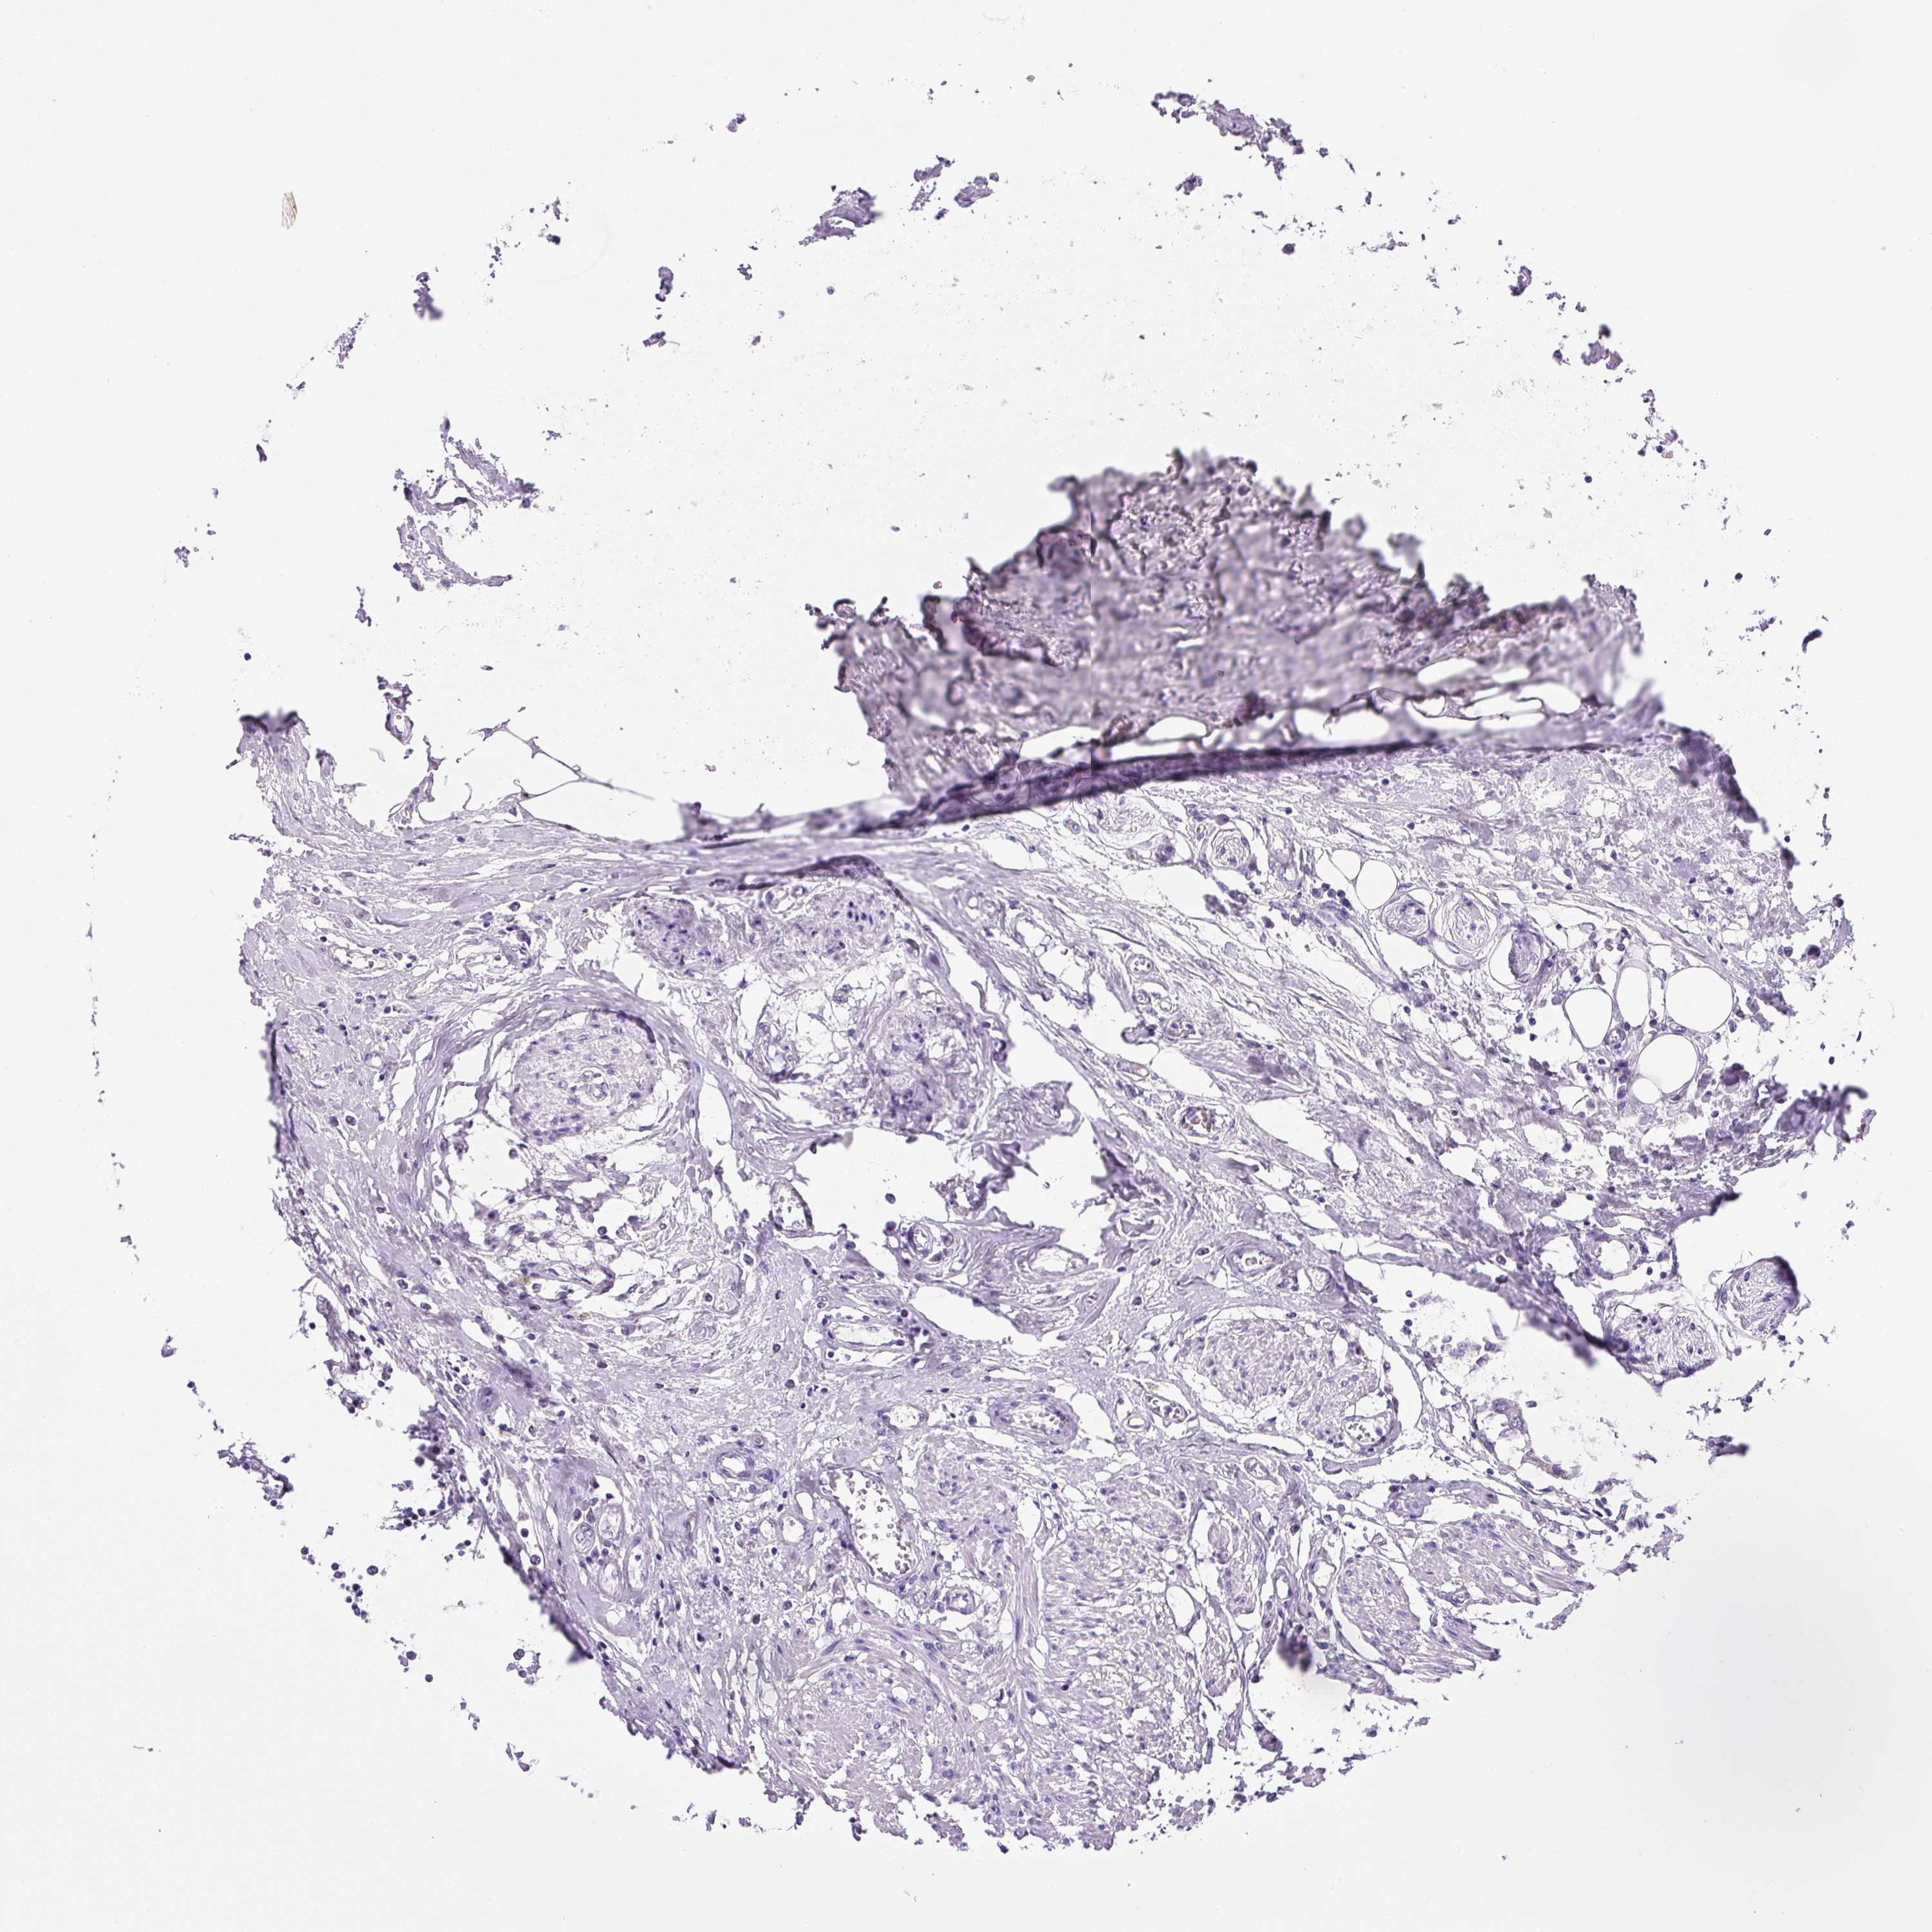

UROTHELIAL CANCER - Protein expressioni

A mouse-over function shows sample information and annotation data. Click on an image to view it in a full screen mode. Samples can be filtered based on level of antibody staining by selecting one or several of the following categories: high, medium, low and not detected. The assay and annotation is described here.

Note that samples used for immunohistochemistry by the Human Protein Atlas do not correspond to samples in the TCGA dataset.

Antibody stainingi

Antibody staining in the annotated cell types in the current human tissue is reported as not detected, low, medium, or high, based on conventional immunohistochemistry profiling in selected tissues. This score is based on the combination of the staining intensity and fraction of stained cells.

Each image is clickable and will lead to virtual microscopy that enables deeper exploration of all samples and also displays staining intensity scores, fraction scores and subcellular localization as well as patient and tissue information for each sample.

Antibody HPA055240

Staining

High

Medium

Low

Not detected

Intensity

Strong

Moderate

Weak

Negative

Quantity

>75%

75%-25%

<25%

None

Location

Nuclear

Cytoplasmic/membranous

Cytoplasmic/membranous,nuclear

Urothelial carcinoma, High grade

Urothelial carcinoma, Low grade